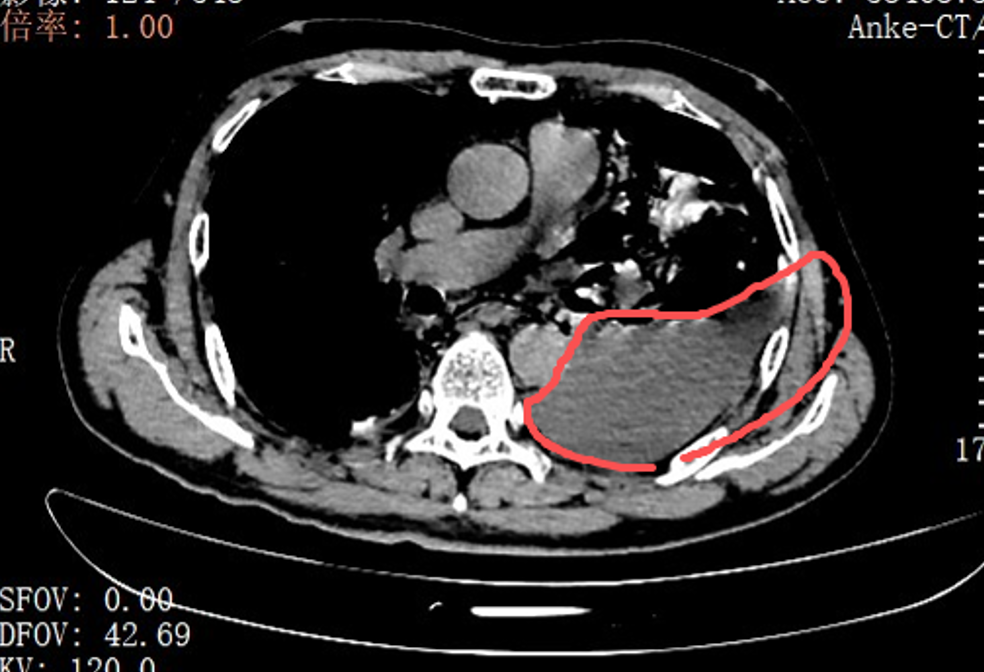

红圈区域是食物残渣、消化液破入食管